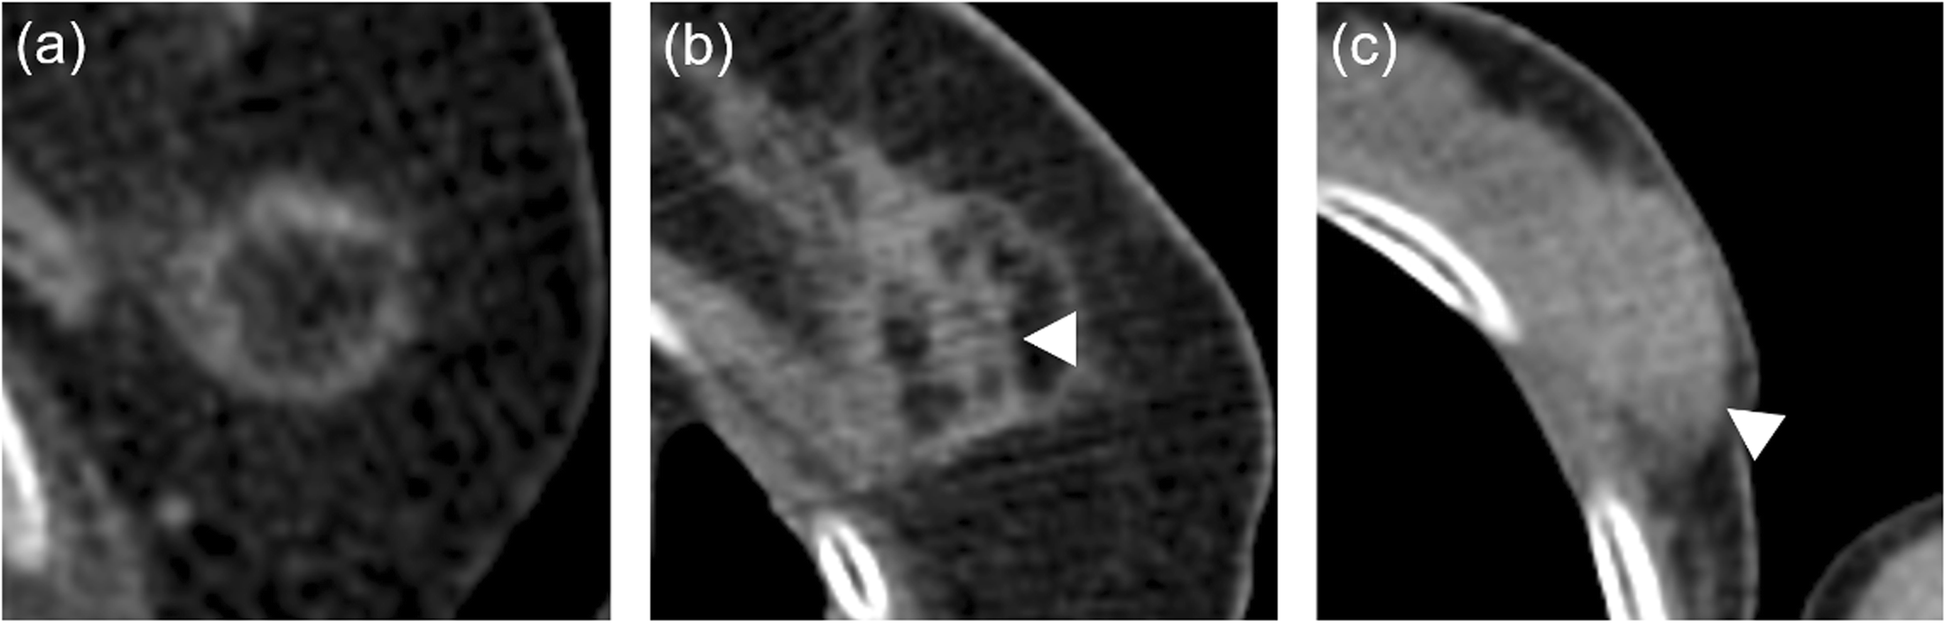

Fig. 1

Classification of CT findings on 18F-FDG PET/CT after breast-cryoablation. CT findings were classified as fatty mass type (a, b) or non-fatty mass type (c). Fatty mass type was defined as the treated area including fat density, including a fatty mass with a soft tissue density septum (b, arrowhead). Non-fatty mass type was defined as the treated area consisting only of soft tissue density (c, arrowhead)